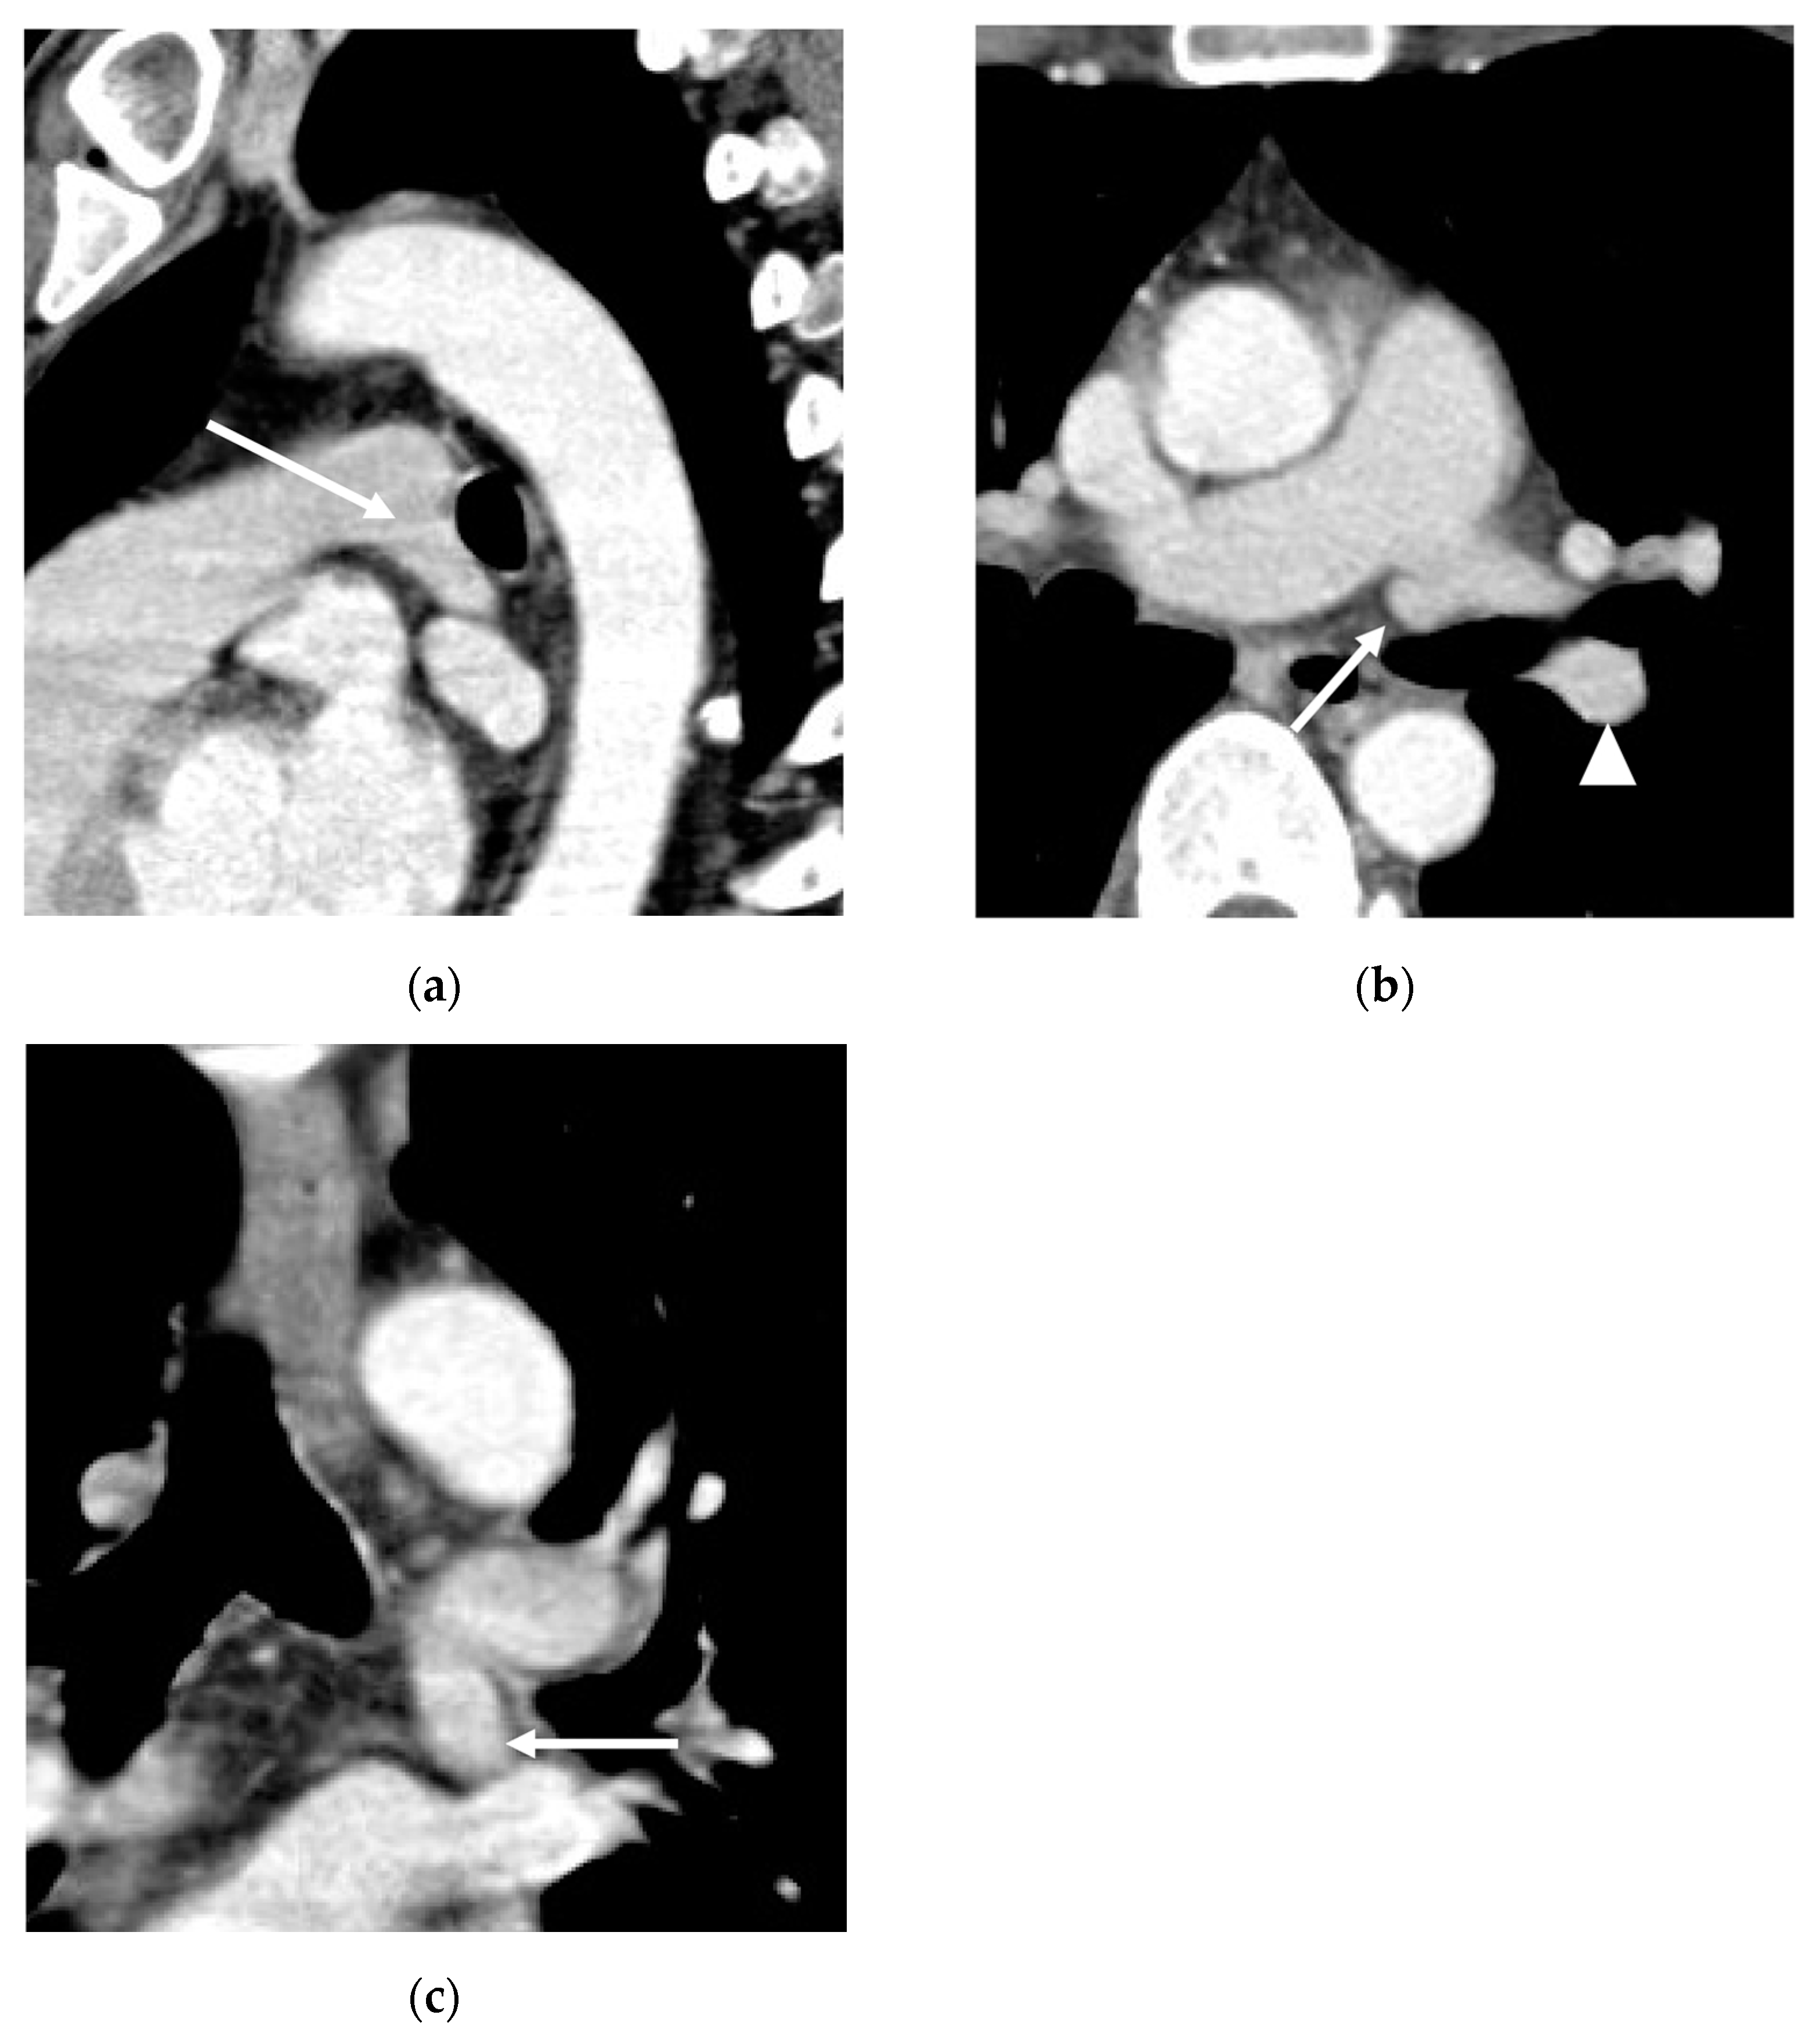

3. Results

3.1. Incidence

3.2. Lobar and Segmental Supply Patternf of the AP

3.3. Diameter of the AP

3.4. Presence of Other Accompanying Variations